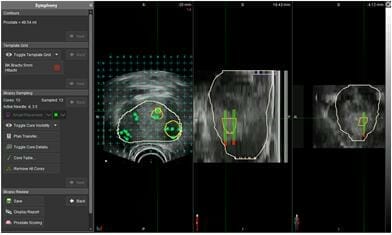

MRI Fusion Guided biopsies of the prostate

Images showing how biopsies are targeted